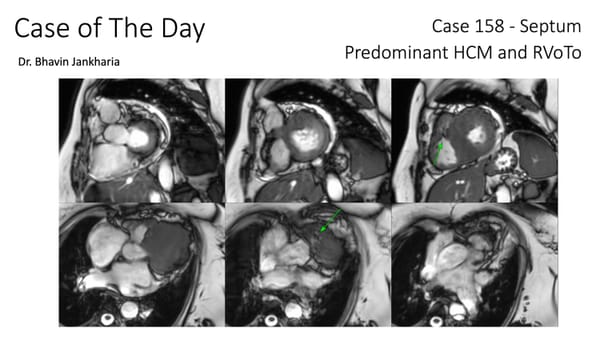

COD 158 - Septum Predominant HCM and RVoTo

RVoTo involvement in HCM is uncommon but diagnosing it may change the management plan and prognosis

By Bhavin Jankharia Jan 26, 2026